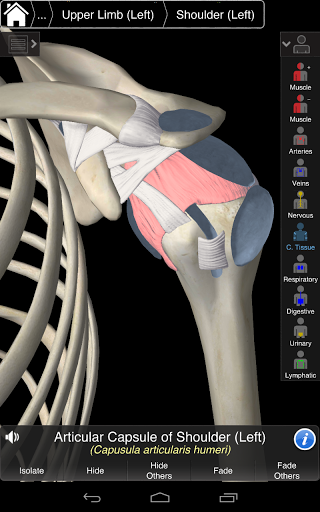

Essential Anatomy 3 jest responsywny, wizualnie oszałamiający i pozbawiony wysiłku. Aplikacja jest w pełni 3D, co oznacza, że możesz zobaczyć dowolną strukturę anatomiczną w izolacji, a także pod dowolnym kątem.

Essential Anatomy 3 został zaprojektowany z myślą o użytkowniku - samo ciało staje się interfejsem. W odróżnieniu od innych aplikacji 3D, które opierają się na wcześniej zdefiniowanych układach anatomicznych i regionalnych rozbiorach, które kierują użytkownikiem, Essential Anatomy 3 3D4Medical pozwala znaleźć to, czego szukasz bez komplikacji.

---- Prawidłowa wymowa audio dla każdej struktury

---- nomenklatura łacińska dla każdej struktury anatomicznej